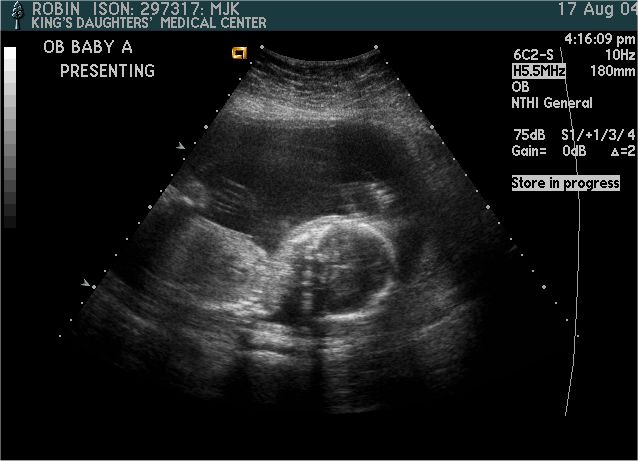

Baby A

Pictures from Ultrasound at 20 weeks.